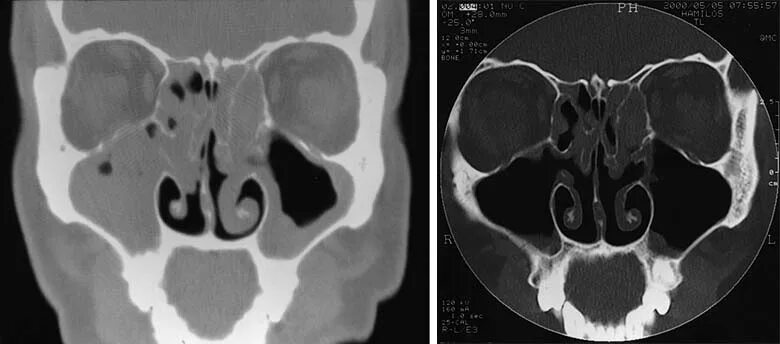

Синусит на кт